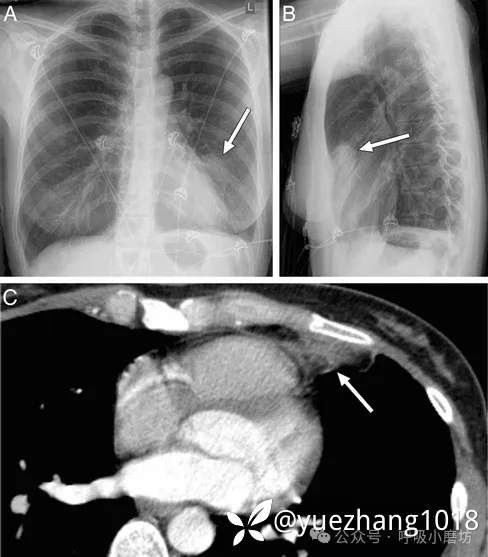

初始后前位胸片未见异常,但侧位片提示胸骨后肿块及左侧少量胸腔积液(图1A)。

图1A 胸部侧位X线摄影: 箭头指向胸骨后肿块;箭标示处指向胸腔积液

考虑到产后情况和D-二聚体轻度升高,完善了CTPA检查,未发现肺栓塞。但于左心膈角见一脂肪密度病灶,周围环绕炎性组织(图1B)。

图1B CTPA显示左心膈角处一脂肪性病变(箭头),周围环绕炎性组织,伴有少量胸腔积液(箭)

经非甾体抗炎药治疗后症状迅速缓解,2周后复查CT显示病灶基本吸收(图1C)。

图1C 两周后CTPA:左心膈角处病灶(箭头所示)已基本完全消退,未见胸腔积液